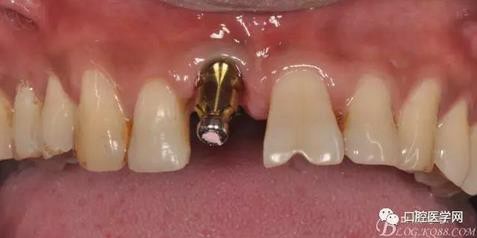

圖19 口內(nèi)修復(fù)基臺(tái)正位照

圖20 口內(nèi)修復(fù)基臺(tái)正位照